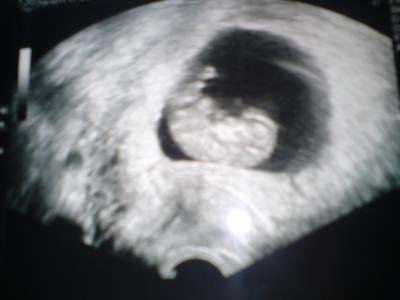

Sooo hatte heute meinen FA Termin uiii es war soo toll,unser Krümel ist jetzt schon 3,6 cm das Herz hat ganz doll geblubbert

Dann erfahre ich noch das ich schon am Freitag in die 12te Woche gehe und ET ist vorgerückt auf den 13.05 hihi

Hier noch das Foto ![]()